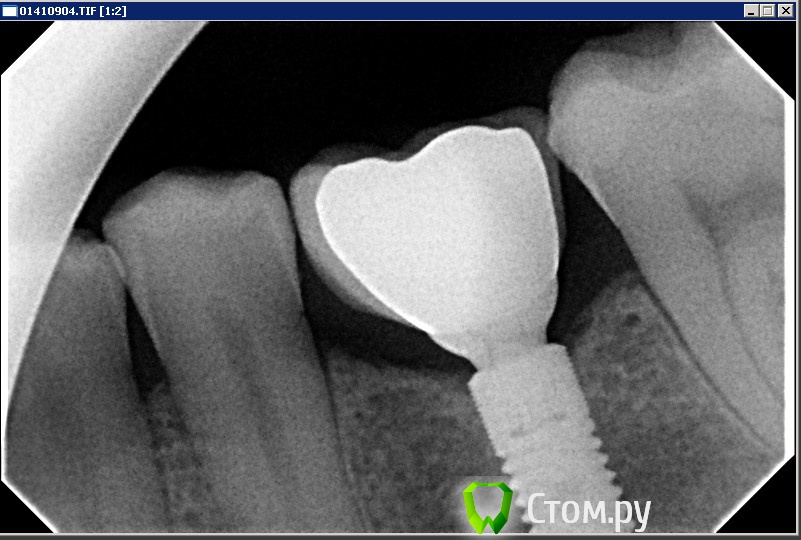

vinstom Опубликовано 3 августа, 2014 Автор Поделиться Опубликовано 3 августа, 2014 Ну вот и закончился этот кейс. Выкладываю фото окончательной работы. Коронка та же, абатмент новый. Была очень сильная перегрузка, и не выверены ведения. Никак не предполагал, что получится такая познавательная беседа. СПАСИБО! P.S. Александр, конечно меня не задела ваша шутка. Улыбнуло. Ссылка на комментарий

Doc Опубликовано 3 августа, 2014 Поделиться Опубликовано 3 августа, 2014 А теперь чисто для порядка сравните кость на первом и последнем снимке. Ответы на многие вопросы, здесь затронутые, станут гораздо очевиднее. Ссылка на комментарий